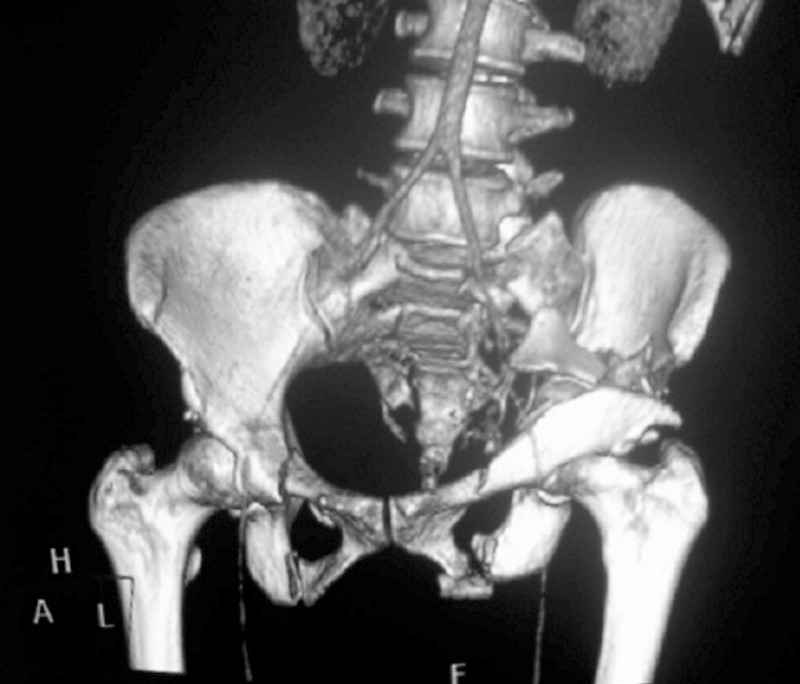

I'm posting this case on behalf of Dr. Pedro Caba, he is unable to post but able to read. 41 yo female , fall from 10 meters five days ago. Hemodynamically unstable on admission treated by angio and embolization and skeletal traction, with no external support. No associated injuries. Based on CT scan the pt has a both column fracture with conminuted dome and displaced anterior column and a sacral Denis 1 fracture with a displaced left ala. I think the best approach for the acetabular fracture is ilioinguinal with Smith-Petersen extension but don't know exactly the sequence . Will you start with the sacral fracture? Which technique? Thanks in advance Pedro Caba Unidad de Trauma Hospital 12 de Octubre Madrid Spain

This complex and displaced sacral injury is likely an H pattern...2 hemipelvic components, an upper sacral component which remains attached to the lumbar spine, and a caudal sacral component...there are typically anterior ring injuries as well...in this patient's example, the left sided acetabulum also has been exploded.

The hemipelvic components' displacements depend on their instability...this patient's left side seems to be the worst.

The transverse fracture limb liberates the upper sacral segment and its attached lumbar-thoracic-cervical spine to displace...usually anteriorly and in kyphosis.

The kyphosis and anterior translation of the upper sacral segment distorts the safe area for iliosacral screw usage...the imaging allows the surgeon to preoperatively plan if iliosacral screw fixation is a safe possibility.